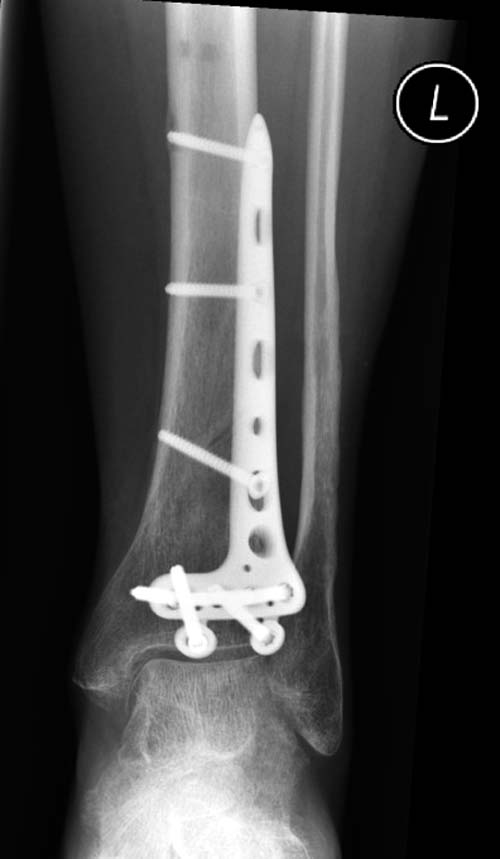

Первый случай, где перелом в результате падения с небольшой высоты, где мортиз рентген снимок показал отстутствие укорочения наружной

лодыжки и КТ срезы подсказали направления атаки. После такой фиксации нет надобности в гипсовой повязке, брейс и через две недели движения в

суставе без нагрузки.